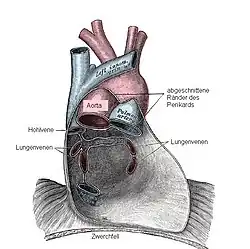

Das Herz liegt innerhalb des Herzbeutels (Perikard) im Mediastinum: Seitlich grenzen, getrennt durch parietale und viszerale Pleura (Brustfell), die linke und rechte Lunge an das Herz. Unten sitzt das Herz dem Zwerchfell auf, das mit dem Herzbeutel verwachsen ist. Oberhalb teilt sich die Luftröhre (Trachea) in die beiden Hauptbronchien (Bifurcatio tracheae), von denen der linke vom Aortenbogen überquert wird. Unterhalb dieser Aufteilung befindet sich der linke Herzvorhof. Wenn dieser krankhaft vergrößert ist, kann das zu einer Spreizung der Hauptbronchien führen, was sich im Röntgenbild als vergrößerter Winkel zwischen den Bronchien darstellt. Der linke Vorhof steht außerdem nach hinten in direktem Kontakt mit der Speiseröhre. Vor dem Herzen befindet sich das Brustbein (Sternum), im oberen Bereich liegt es vor den abgehenden großen Gefäßen. Zwischen Brustbein und Herz liegt der Thymus.

Das Herz liegt also praktisch direkt hinter der vorderen Leibeswand in Höhe der zweiten bis fünften Rippe. Die Herzbasis oben reicht nach rechts etwa zwei Zentimeter über den rechten Brustbeinrand hinaus. Unten kommt die Herzspitze knapp an eine gedachte senkrechte Linie heran, die durch die Mitte des linken Schlüsselbeins verläuft (linke Medioklavikularlinie).

Wandschichten

Das Herz wird vollständig vom bindegewebigen Herzbeutel (Perikard, Pericardium fibrosum) umschlossen. Die untere Seite des Herzbeutels ist mit dem Zwerchfell (Diaphragma) verwachsen, so dass die Bewegungen des Zwerchfells bei der Atmung auf das Herz übertragen werden. Die innerste Schicht des Herzbeutels (Pericardium serosum) schlägt am Abgang der großen Blutgefäße (s. u.) in das Epikard um, das dem Herzen direkt aufliegt. Zwischen Perikard und Epikard liegt ein mit 10–20 ml Flüssigkeit gefüllter kapillärer Spaltraum, der reibungsarme Verschiebungen des Herzens im Herzbeutel ermöglicht.

Unter dem Epikard befindet sich eine Fettschicht (Tela subepicardiaca), in der die Herzkranzgefäße verlaufen. Nach innen hin folgt die dicke Muskelschicht (Myokard) aus spezialisiertem Muskelgewebe, das nur im Herzen vorkommt. Die Herzinnenräume werden vom Endokard ausgekleidet, das auch die Herzklappen bildet.

In den rechten Vorhof münden die obere und untere Hohlvene (Vena cava superior und inferior). Sie führen das sauerstoffarme Blut aus dem großen Kreislauf (Körperkreislauf) dem Herzen zu. Zwischen rechtem Vorhof und rechter Kammer befindet sich die Trikuspidalklappe, die bei der Kammerkontraktion einen Rückstrom des Blutes in den Vorhof verhindert. Von der rechten Herzkammer aus fließt das Blut über einen gemeinsamen Stamm (Truncus pulmonalis) in die beiden Lungenarterien. Der Rückfluss in die rechte Kammer wird durch die taschenförmige Pulmonalklappe verhindert. Die Lungenarterien führen das sauerstoffarme Blut dem Lungenkreislauf (kleiner Kreislauf) zu.

Durch meist vier Lungenvenen fließt das in der Lunge mit Sauerstoff angereicherte Blut in den linken Vorhof. Von hier aus gelangt es über eine weitere Segelklappe, die Mitralklappe, zur linken Kammer. Der Ausstrom erfolgt durch den sogenannten linksventrikulären Ausflusstrakt (LVOT) über eine weitere Taschenklappe (Aortenklappe) und die Hauptschlagader (Aorta) in den Körperkreislauf.